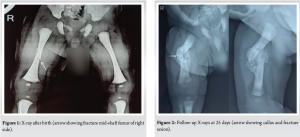

A 31-year-old booked primigravida, with regular and normal antenatal care clinics, presented in the emergency room with premature rupture of membrane (PROM) with breech presentation at 38 weeks and 4 days period of gestation, underwent emergency cesarean section. She had normal initial antenatal scans. Her medical history was insignificant and negative for diabetes, hypertension, or any previous uterine surgery. The patient was offered Spinal anesthesia. An appropriate wider incision was made at the lower uterine segment. The fetus was extracted after catching hold of footling, extending and rotating the lower limbs to align the fetal pelvis anteroposteriorly, followed by application of fundal pressure on the uterus to deliver the rest of the baby with lateral flexion. The delivery was difficult due to the large size of the fetus and anhydroamnios secondary to PROM, a force was applied for the rotation of the limbs. However, the operating surgeon and assisting nurse didn’t hear any “crack” or “snap” during extracting the fetus. A 3915 g male infant, large for gestational age, was delivered and cried after birth. APGAR scores at 1 and 5 min were 8 and 9, respectively. On examination, the attending pediatrician noticed diffuse swelling and deformity in the right mid-thigh, restricted right leg movements, and excessive cry on palpation, which raised a high suspicion of a fracture shaft of the right femur in the neonate. A thorough clinical examination revealed no other abnormalities. An immediate orthopedic consultation was done. The right thigh was found to be swollen, externally rotated and shortened; bony crepitus of the femur was palpable with painful passive movements. Distal pulsations were intact. Anteroposterior and lateral view X-rays of the right thigh revealed a displaced spiral fracture of the middle-third shaft femur (Fig. 1). Bone structure and mineralization appeared normal. There was no blue sclera, other bone fractures or limb deformity, thus any possibility of osteogenesis imperfecta was ruled out. The baby’s right lower limb was immobilized with a 90–90 posterior splint and shifted to the neonatal intensive care unit. Paracetamol drops (12 mg/kg) three times a day was advised for pain relief. Parents were informed of this untoward complication and counseled.

The next day, the baby was handed over to the mother and was kept on breastfeeding. After 5 days post-operative, both the mother and neonate were discharged and reviewed in the orthopedic outpatient department after 1 week, when the posterior splint was replaced with a toe-groin cast for another 2 weeks. On follow-up on the 25th day, a repeat X-ray showed abundant callus between fracture ends, and the cast was removed (Fig. 2). Clinical examination revealed no local tenderness and deformity with active, painless movements of both limbs, thus completing the treatment. At follow-up after 10 months, repeat X-ray shows complete healing of the fracture with no deformity and visible limb length discrepancy of the limb (Fig. 3).